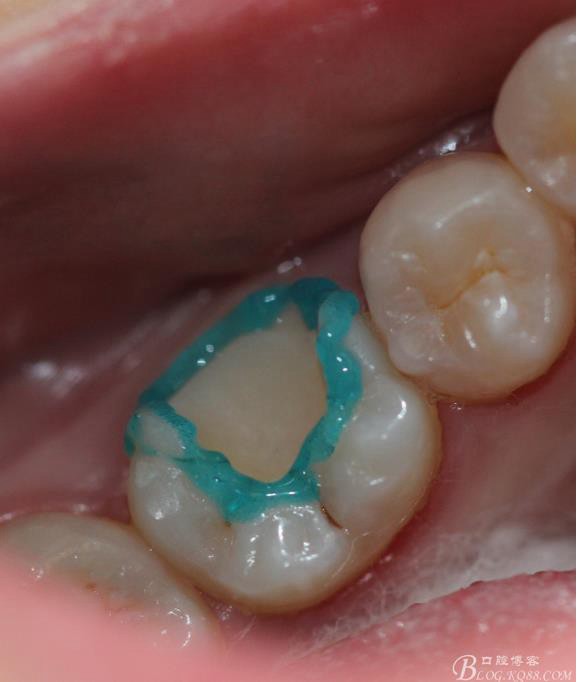

牙體隔濕酸蝕 牙釉質(zhì)15s 牙本質(zhì)20s進(jìn)行濕粘接(不要吹太干)

粘接 去除多余的粘結(jié)劑 進(jìn)行光照 調(diào)HE 一周后進(jìn)行拋光